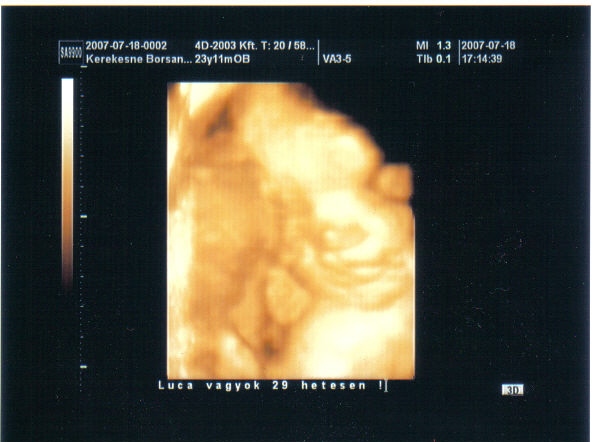

Linácska, Tündi: a babák nagyon hasonlítanak egymásra,